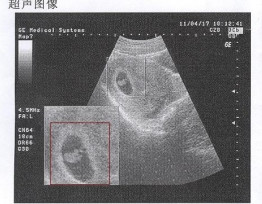

B超

B超检查只能在妊娠5周后可以看见孕囊,妊娠6周时妊娠囊检出率达100%。妊娠6~7周可见胚芽,孕49天,胚芽径线2mm时可见原始心管搏动,妊娠8周初具人形。过早做B超,是不容易见孕囊的影子。